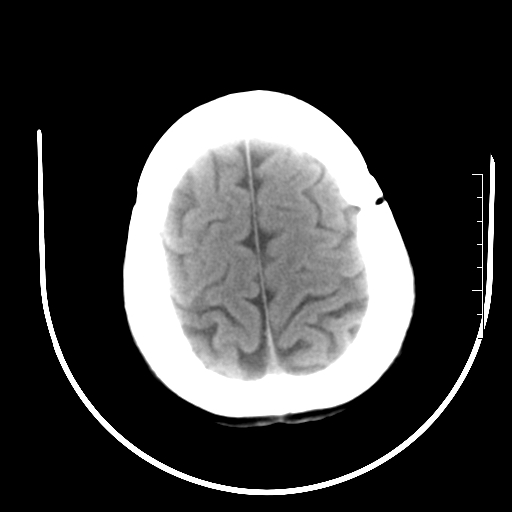

标题: CT27880:f、55y,头痛。 [打印本页]

标题: CT27880:f、55y,头痛。

考虑左侧顶部镰旁脑膜瘤;建议行ct增强扫描检查。

考虑左侧顶部镰旁脑膜瘤,建议行ct增强扫描检查。

考虑左侧顶部镰旁脑膜瘤;建议行ct增强扫描检查

大脑镰旁脑膜瘤可能,建议增强或mri

镰旁小脑膜瘤可能性大

左侧顶部镰旁脑膜瘤,增强